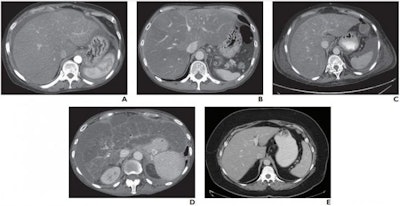

Dr. Meghan G. Lubner from the department of radiology at the University of Wisconsin School of Medicine and Public Health and colleagues reviewed 186 patients with biopsy-proven NAFLD who underwent CT within one year of biopsy to determine the utility of laboratory and CT metrics in identifying patients with high-risk NAFLD.

The researchers found 87 patients (47%) had NASH and 112 (60%) had moderate to severe steatosis. They classified a total of 51 patients as fibrosis stage F0, 42 as F1, 23 as F2, 37 as F3, and 33 as F4. The researchers also determined 70 (38%) had advanced fibrosis (stage F3 or F4) and were considered to have high-risk NAFLD.

In terms of the laboratory and CT metrics, a FIB-4 score showed correlation with fibrosis, and so did liver segmental volume ratio and splenic volume on CT. Lubner and her team found FIB-4 and subjective scores were complementary, and FIB-4 performed best for NASH assessment.